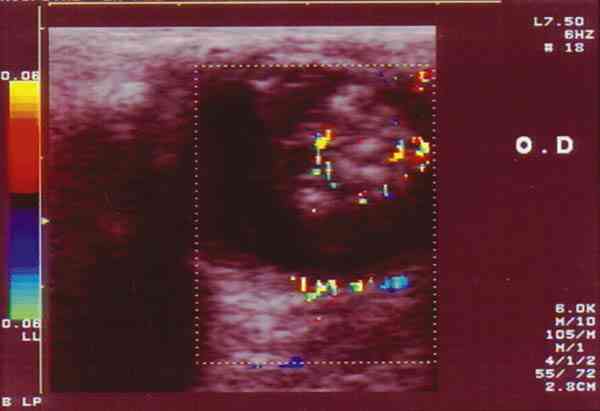

El RB con gran frecuencia adopta en Ecografía (figura 1) un patrón típico

que consiste en una masa única o múltiple, heterogénea, con presencia de

calcio y desprendimiento de retina. Cuando esto ocurre, permite el diagnóstico

en el 100% de los casos (4).

Figura 1. A. RTB lobulado con área calcificada y pequeñas zonas de

necrosis. B. Control post-quimioterapia. Masa residual con calcificación

masiva.

El empleo del Doppler (5,6), que por lo general es capaz de detectar vasos en

los tumores no calcificados, permite diferenciarlo de una hemorragia, enfermedad

de Coats o retinopatía del prematuro que por el contrario no presentan flujos

(figuras 2-7).

Figura 2. Retinoblastoma parcialmente calcificado que llega hasta el

cristalino. Mediante el color se aprecia vascularización intratumoral.